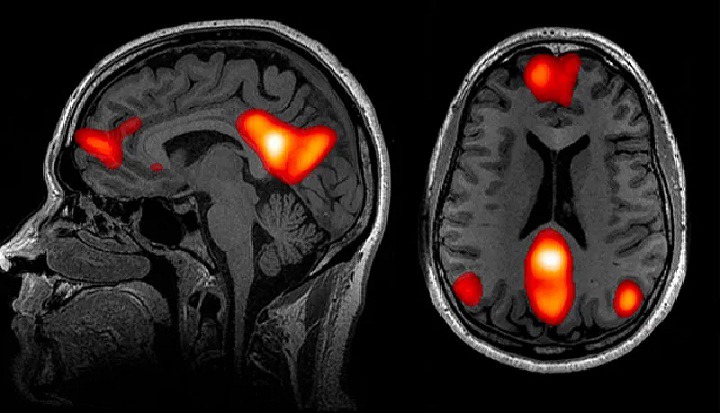

طبق پژوهش آنها که نتایجش در سال ۲۰۲۰ در ژورنال علمی «نیچر کامیونیکیشنز» منتشر شد، نقطه حساس تنهایی مغز در درون شبکه پیشفرض (default network) قرار دارد. شبکه پیشفرض بخشی از مغز است که وقتی از نظر ذهنی در حالت آمادهباش هستیم، فعال میشود. بزدوک میگوید: «تا ۲۰ سال پیش حتی نمیدانستیم که این سیستم را داریم.» ولی تحقیقات مشخص کردهاند که فعالیت در شبکه پیشفرض بیشترین میزان مصرف انرژی در مغز را دارد.

بزدوک و تیمش نشان دادند که برخی از مناطق شبکه پیشفرض در افراد دچار تنهایی مزمن بزرگترند و با بخشهای دیگر مغز نیز ارتباط قویتری دارند. شبکه پیشفرض در بسیاری از تواناییهای متمایزی که در انسانها تکامل یافتهاند مانند زبان، پیشبینی آینده و استدلال عِلّی (causal reasoning) دخیل است. در کل شبکه پیشفرض زمانی فعال میشود که به دیگران فکر میکنیم، مثلا زمانی که منظور آنها را تفسیر میکنیم.

تحقیقات درباره اتصال شبکه پیشفرض، شواهد تصویربرداری عصبی را ارائه کرد که اکتشافات قبلی روانشناسان را تأیید میکرد. اکتشافاتی که طبق آن افرادِ تنها تمایل دارند که درباره تعاملات اجتماعی رؤیاپردازی کنند، بهراحتی برای رویدادهای اجتماعی گذشته دلتنگ شوند و حتی حیوانات خانگی خود را مانند انسان تصور کنند؛ مثلا با گربه خود طوری صحبت کنند که گویی انسان است. بزدوک میگوید: «برای انجام این کار نیز به شبکه پیشفرض نیاز داریم.»

دادههای اخیر تصویربرداری مغز نشان میدهند که تنهایی عمیقا در روان ما ریشه دارد. لیویا تومووا (Livia Tomova)، دستیار پژوهش علوم اعصاب در دانشگاه کمبریج، و همکارانش از ۴۰ نفر خواستند که ۱۰ ساعت چیزی نخورند. سپس درحالیکه به تصاویر غذاهای اشتهابرانگیز نگاه میکردند، مغزشان را اسکن کردند. بعد همان داوطلبان ۱۰ ساعت را تنها سپری کردند بدون گوشی، ایمیل یا حتی کتاب داستانی که بتواند جایگزینی برای ارتباط با دیگران باشد. سپس دوباره مغز آنها اسکن شد، ولی این بار درحالیکه به تصاویری از گروههای شادی از دوستان نگاه میکردند. دانشمندان با مقایسه اسکن مغز این افراد مشاهده کردند که الگوهای فعالسازی مغز در زمان گرسنگی و در زمان احساس تنهایی بسیار شبیهاند.